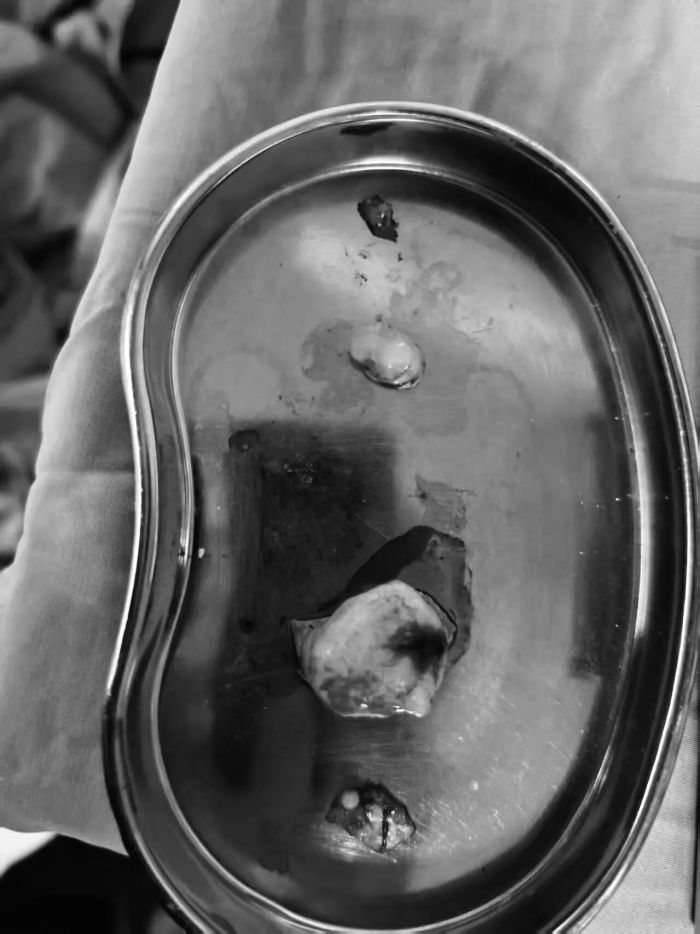

脑部手术被誉为“在毫厘之间刀尖起舞”,更何况是同时切除4颗肿瘤,对手术精度和医生技术有着极高要求。手术当天,神经外科副主任廖鑫、主治医师刘永茂及其医护团队默契配合,借助显微镜与神经内镜的协同优势,精准定位肿瘤位置,小心翼翼地分离肿瘤与周围脑组织、神经血管,避开重要功能区,逐一将4颗肿瘤完整摘除。整个手术过程顺利,出血少、创伤控制精准。经病理学检查,四颗肿瘤均为良性肿瘤,患者预后较好。